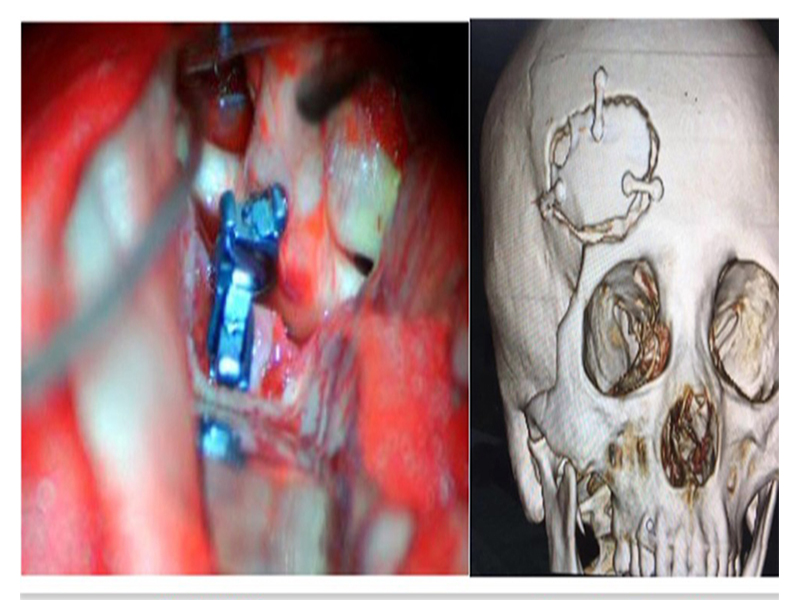

56 4 CT

()